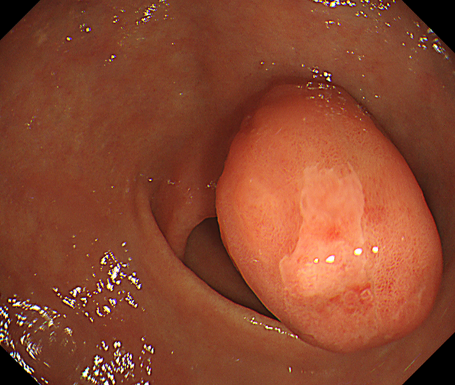

• 内視鏡検査

粘膜下腫瘍とは粘膜の下(粘膜下層~固有筋層)に発生する腫瘍のことを指します。食道~大腸までどの部位でも発生します。

消化管間質腫瘍(Gastrointestinal stromal tumor:GIST)は、固有筋層に発生する粘膜下腫瘍の一種です。頻度としては10万人に1〜2人と稀な腫瘍で、本邦においては胃に多い(胃→小腸→大腸、食道の順)と言われています。男女差はなく、中高年に多い傾向があります。